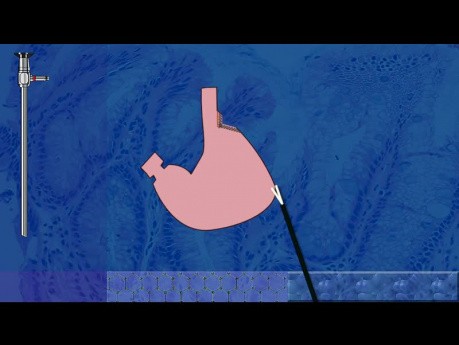

Application - Tutoriel Fundoplicature Géométrie

Dans cette vidéo nous expliquons en détail l'utilisation de notre application Fundoplicature Géométrie dans la fermeture du hiatus œsophagien lors de la prise en charge laparoscopique d'une hernie hiatale...

Traitemennt chirurgical d'une hernie hiatale...

Dans cette vidéo nous apprenons la technique de la gastroplastie selon Wedge-Collis comme le traitement l'œsophage court lors de la réparation laparoscopique d'une hernie hiatale et d'une fundoplastie...